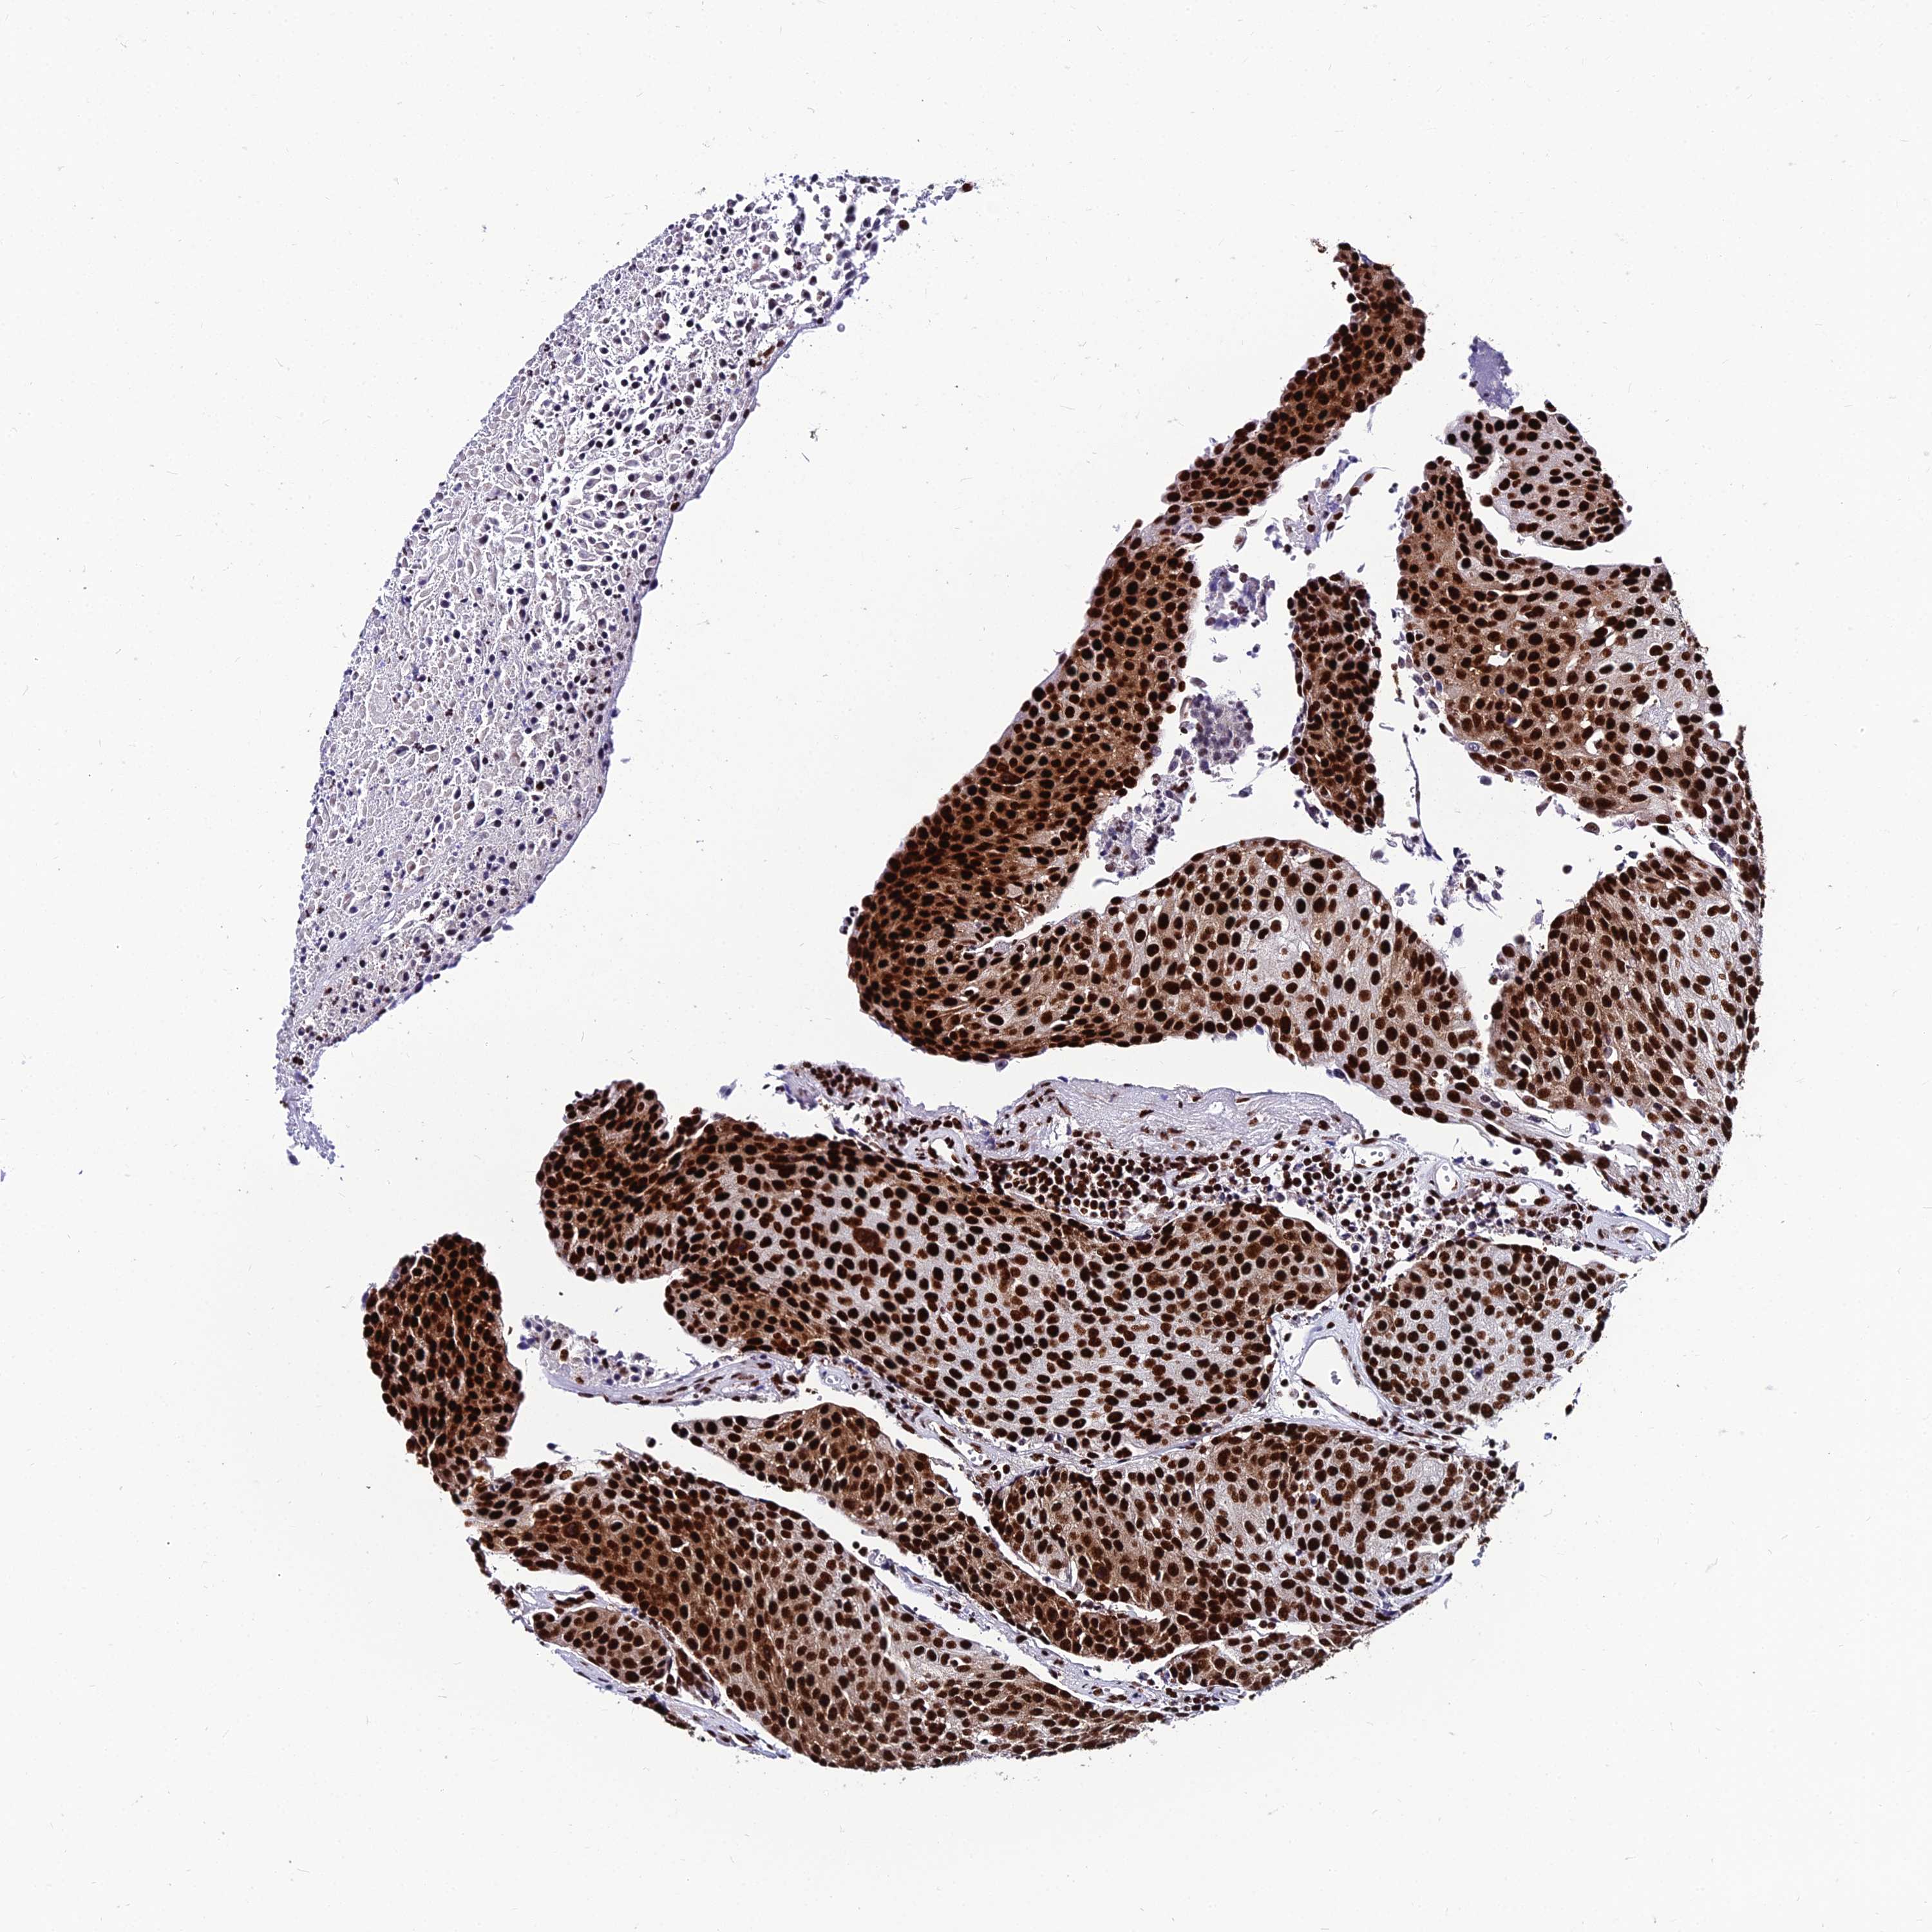

UROTHELIAL CANCER - Protein expressioni

A mouse-over function shows sample information and annotation data. Click on an image to view it in a full screen mode. Samples can be filtered based on level of antibody staining by selecting one or several of the following categories: high, medium, low and not detected. The assay and annotation is described here.

Note that samples used for immunohistochemistry by the Human Protein Atlas do not correspond to samples in the TCGA dataset.

Antibody stainingi

Antibody staining in the annotated cell types in the current human tissue is reported as not detected, low, medium, or high, based on conventional immunohistochemistry profiling in selected tissues. This score is based on the combination of the staining intensity and fraction of stained cells.

Each image is clickable and will lead to virtual microscopy that enables deeper exploration of all samples and also displays staining intensity scores, fraction scores and subcellular localization as well as patient and tissue information for each sample.

Antibody HPA001359

Antibody HPA016884

Antibody CAB032820

Staining

High

Medium

Low

Not detected

Intensity

Strong

Moderate

Weak

Negative

Quantity

>75%

75%-25%

<25%

None

Location

Nuclear

Cytoplasmic/membranous

Cytoplasmic/membranous,nuclear

Urothelial carcinoma, High grade

Urothelial carcinoma, Low grade

Adenocarcinoma, NOS